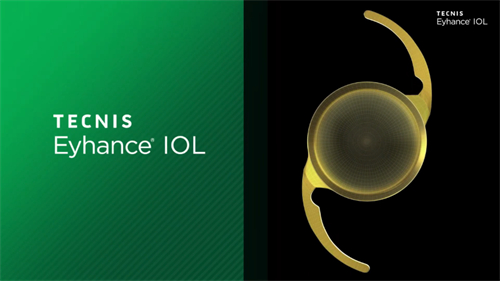

其他眼病:复杂白内障、青光眼、角膜炎等

小创口玻璃体切割术:使用25G/27G超小创口系统,创伤小、修复快

复杂性视网膜脱离复位术:成功概率高,术后视力修复良好

黄斑手术:包括黄斑前膜剥除、黄斑裂孔修复等

眼内注药术:治疗黄斑水肿、新生血管等